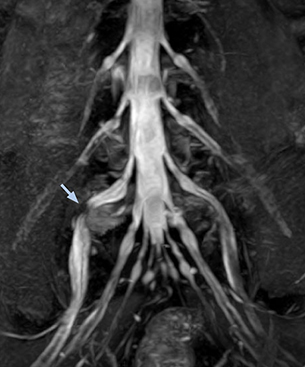

“In such case, we would then browse through axial T2-weighted MR images slice by slice and mentally reconstruct the actual situation based on both radiculography and MRI. Fortunately, NerveVIEW can now very well show nerve courses and presence of nerve compression or edema in one single image series.” “We have often seen NerveVIEW directly depict details of the nerve compression that were not observed by radiculography. Therefore, we think that with NerveVIEW we can reduce the number of invasive examinations, especially for some patients with lumbar plexus symptoms.”

“Before NerveVIEW, diagnosis by MRI alone was sometimes difficult, unless there was a strong suspicion based on clinical symptoms,” says Shoji Yabuki, MD, DMSc, Orthopedic surgeon at Fukushima Medical University School of Medicine. “This is why we routinely perform selective lumbosacral radiculography (nerve root block) and x-ray in such cases. However, radiculography can only depict nerves as far as the contrast agent reaches. When a nerve is distorted by compression, the contrast agent will not pass through this compressed area, preventing us from evaluating the full nerve compression.”

The key concept in MR neurography, Dr. Yabuki stresses, is the ability to directly visualize spinal nerves, versus inferring the presence of pathology indirectly. “Before NerveVIEW, we estimated compression of the nerve by looking for the presence or absence of fat signal on other MR images,” he says.

“For example, in sagittal images, when the presence of fat is observed in the intervertebral foramen, it suggests that there is a margin around the nerve. Similarly, the absence of fat indicates that the nerve is being compressed. So, we used to deduce nerve compression indirectly. With NerveVIEW, however, we can observe the condition of the nerves directly, regardless of the presence or absence of fat. We always prefer such direct observation of anatomy over having to make an inference about it.”